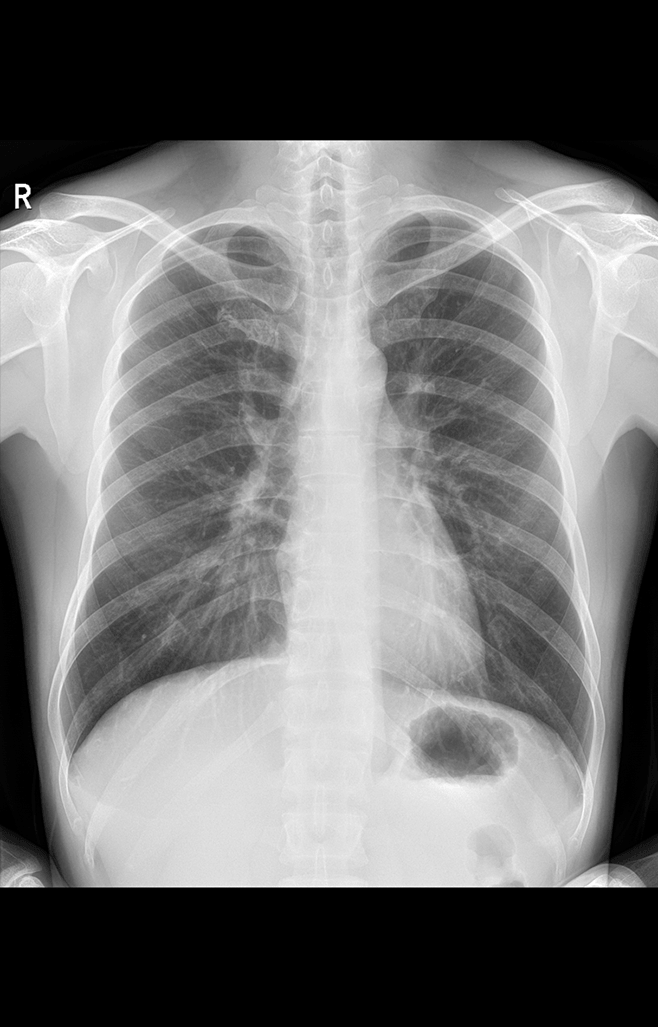

多功能诊断专用动态DR

太阳成集团tyc122cc入口科技全新设计的第四代床式动态DR,集拍片、透视、造影、全身拼接、尘肺体检于一体,一机多能,真正意义上实现全科室应用,提升医院实际效益。

高清动态平板探测器

搭载自主研发超清大视野动态平板探测器,600微米碘化铯大幅提升X线转化效率,独特的非晶硅阵列与高速读取集成电路紧密协作,轻松实现多帧率透视与高清点片。

专业的影像处理系统

“腾灵”系列搭载的IEAE影像处理系统,具备多项发明专利。本系统采用多频域图像处理技术,其6大核心处理模块使影像具有优秀的一致性、柔和性、空间层次感和纹理细腻度,为用户精准诊断病灶奠定了坚实的基础。